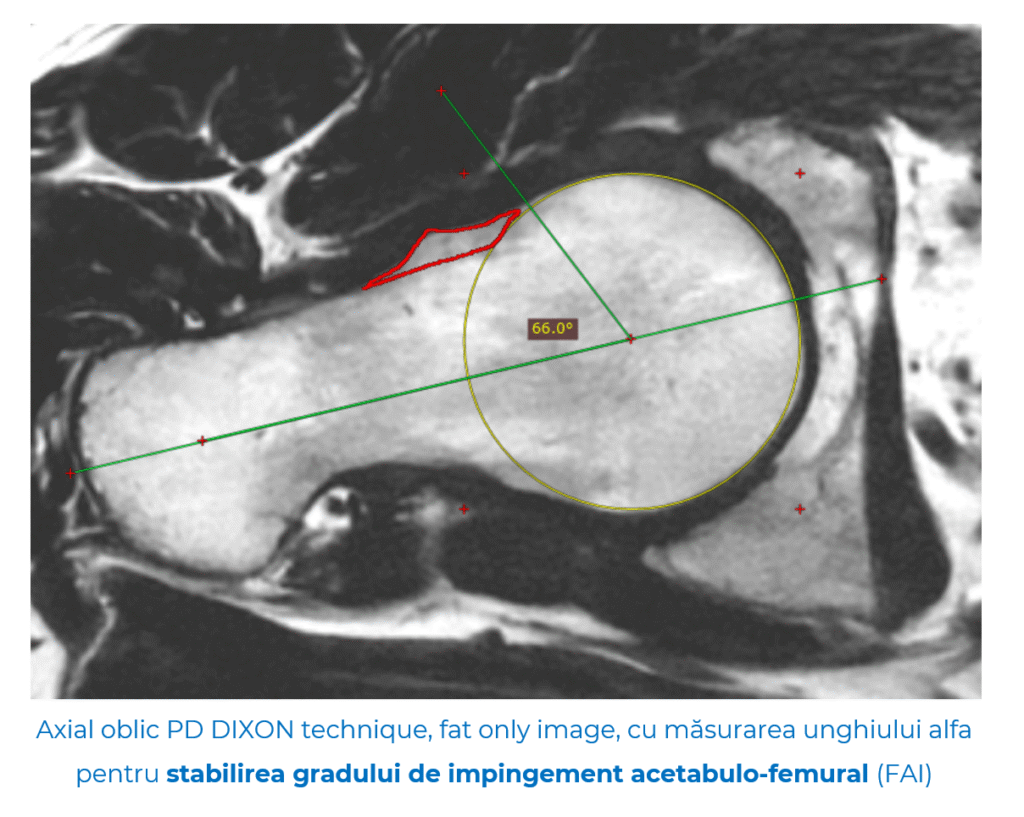

- Impingement femuro-acetabular (FAI)

Această afecțiune apare atunci când capul femural sau marginea acetabulului (cavitatea șoldului) produc o frecare repetată la mișcare, prococând durere, limitarea mobilității și, în timp, afectarea cartilajului.

FAI este greu de observat pe radiografii simple și, adesea, necesită secvențe RMN speciale sau chiar artro-RM (RMN cu substanță de contrast intravenoasă).

- Tomografia computerizată (CT) – oferă detalii precise despre forma și structura osoasă, în special utile în impingementul femuro-acetabular, unde chiar și mici variații anatomice pot conta.

Secvența ZTE aduce un avantaj major în diagnosticul impingementului femuro-acetabular, unde modificările osoase fine fac diferența. În combinație cu RMN-ul convențional și artro-RMN-ul, permite o evaluare completă: os, labrum și cartilaj. Această abordare integrată oferă un diagnostic mai precis și un plan terapeutic personalizat.